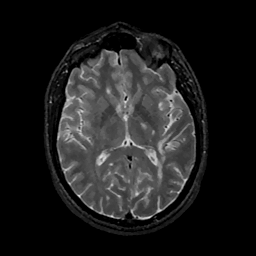

MR Study #11, May 5, 1991 -- Slice #26